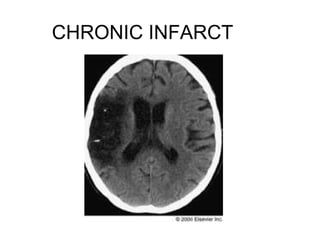

INFARCT??

CHRONIC INFARCT